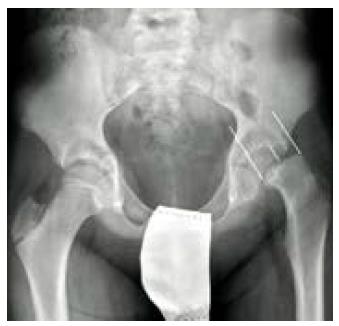

La EFP es una urgencia quirúrgica y sus objetivos principales son detener y evitar la progresión del deslizamiento de la epífisis y prevenir complicaciones. El tratamiento es quirúrgico y dependerá del grado de deslizamiento epifisario y el tiempo de evolución del cuadro clínico.

El tratamiento estándar para EFP estable es la fijación in situ con tornillos. La reducción cerrada no está indicada para casos, debido a que la continuidad entre la epífisis y la metáfisis no se ha interrumpido, el intento de reducción puede fallar y existe el riesgo de lesiones iatrogénicas. En EFP estable se pueden emplear también osteotomías para mejorar la posición de la epífisis en relación con el acetábulo. Estos métodos tienen una alta tasa de éxito a largo plazo, con un riesgo mínimo de complicaciones 18,21.

El caso de EFP inestable es mucho más severa ya que la epífisis se separa de la metáfisis comprometiendo la irrigación de la epífisis con el riesgo de necrosis avascular ulterior. Las alternativas de tratamiento y el tiempo de cirugía son temas de controversia; sin embargo, el procedimiento Dunn modificado es una opción terapéutica que ha ganado popularidad y consiste en una luxación quirúrgica de la cadera que ayuda a restaurar la alineación del fémur proximal; esta ha demostrado resultados favorables con respecto a las tasas de necrosis avascular, resultado funcional y el desarrollo de la osteoartritis radiográfica 21,22.